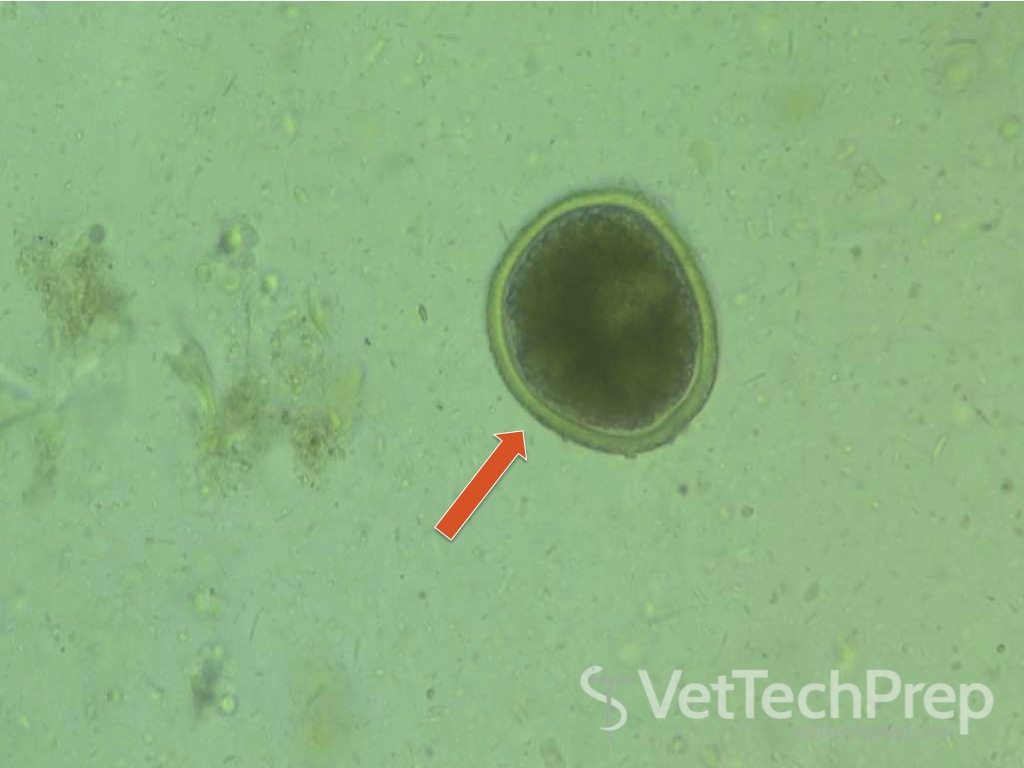

Coccidia

Not zoonotic

Isospora

(common in puppies and kittens)